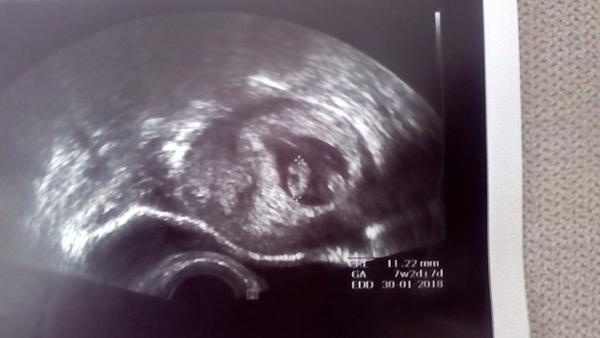

Gratuluju!!!🙂 to je krasny!!! Moc drzim pesti dal! Hlavne ze srdicko bije a vse jde jak ma!🙂